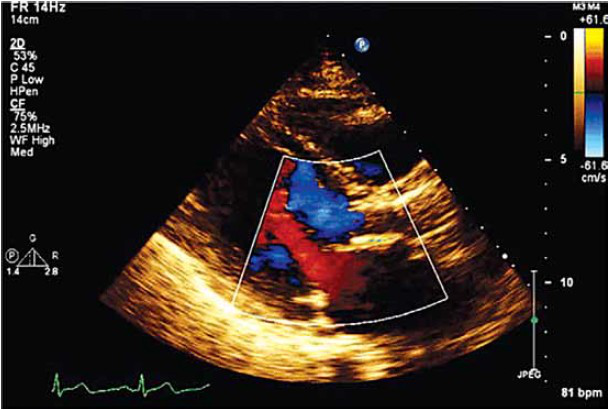

Paciente, 67 anos, sexo feminino, com história de dispneia aos moderados esforços, edema de membros inferiores e palpitações de início há 6 meses. Ao exame físico cardiológico: ritmo cardíaco regular, sopro diastólico aspirativo decrescente com B2 hipofonética, Sopro mesossistólico de hiperfluxo ruflar.

Realizou os exames complementares a seguir: